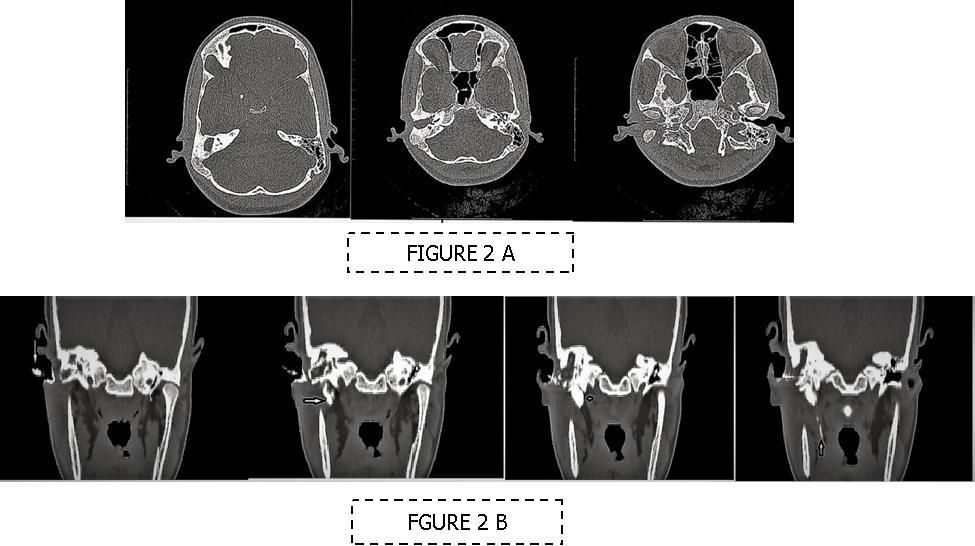

A 13 year old girl presented in ENT outpatient department with complains of recurrent right ear purulent discharge from pre and post auricular area for last 5 years. She had a history of incision and drainage in right post auricular area six months prior for similar complain. On local examination, there was right Grade II8microtia with atretic External Auditory Canal (EAC) and pre-auricular skin tag (Figure 1). A small fistulous opening was also seen in right cavum conchae region. Left ear examination was normal with intact tympanic membrane. Tuning fork tests using 256 and 512 Hz tuning forks showed moderate to severe conductive hearing loss in right ear with Rinne’s test positive in left ear. HRCT scan of temporal bones showed membranous atresia of right EAC with grade II microtia. Soft tissue density was seen filling the EAC and the entire middle ear cavity (Figure 2A). A CT based fistulogram done four months before our consultation identified multiple fistulous tracts situated in post auricular region and anterior to stylomastoid foramen in inframastoid region. These fistulous tracts were communicating through middle ear cavity (Figure 2B). There was associated erosion of posteroinferior and anteroinferior wall of EAC. Ossicles were dysplastic or eroded. Inner ear structures were normal. Patient underwent right radical mastoidectomy with wide conchal meatoplasty under general anaesthesia. Intraoperatively, there was right EAC membranous atresia with fistulous opening in cavum conchae. Cholesteatoma sac was seen filling the mastoid antrum area extending into middle ear cavity and EAC with erosion of posterior canal wall. Except remnant of malleus head which was fixed to epitympanic wall, no other ossicle was found. Oval window area showed bony depression without any overlying stapes footplate (Figure 3). Lateral semicircular canal bulge, facial nerve canal and chorda tympani were found at their usual locations (Figure 4). Obliteration of mastoid cavity posterior to vertical segment of bony facial canal was done using pedicled temporalis muscle flap to reduce the size of postoperative cavity. Middle ear cavity was covered with temporalis fascia graft.

Figure 2.(A-B) HRCT imaging. (A) Right canal atresia with soft tissue density behind it (B) CT sino-gram showing multiple (arrow marked) sinuses communicating to right middle ear cavity.